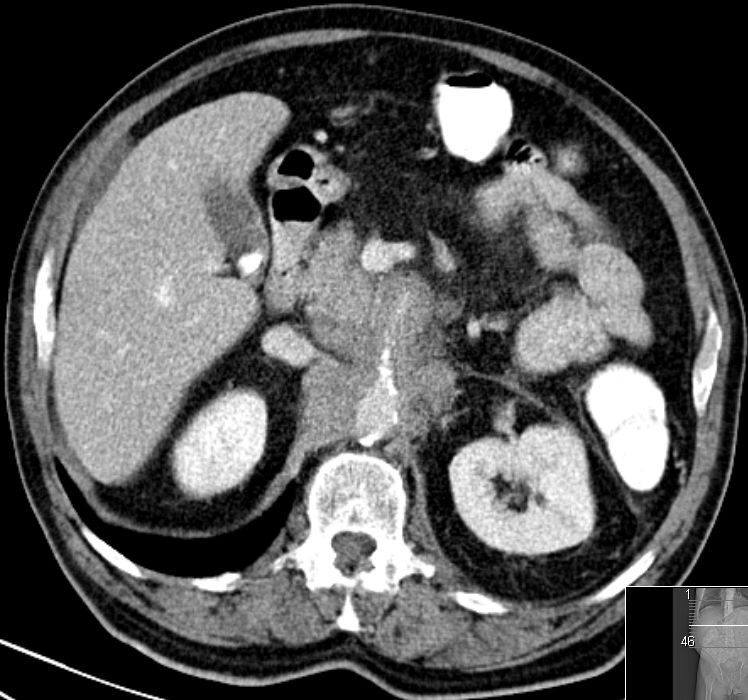

| V. mesenterica superior | 69-jährige Frau mit Pankreaskopfkarzinom. Das CT zeigt eine Infiltration der Vena mesenterica superior.

Nach Laparotomie inoperabel. Infiltrate an der Mesenterialwurzel. Bilidigestive Anastomose, Gastrojejunostomie, Cholezystektomie.![]() | |